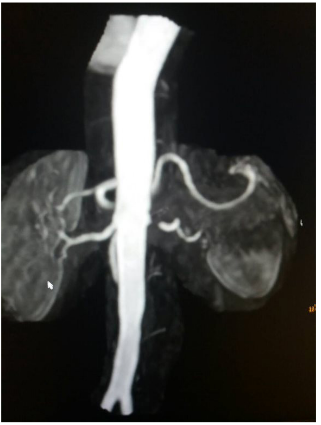

The acceleration time 0,12s (AT:<0,07sec), indicative renal low flow. The patient was then subjected to magnetic angiography of renal arteries (MRA) confirming the triplex’s findings: 90% stenosis of left renal artery immediately after the outgrowth of the abdominal aorta (Figure 4). In the radioactive nephrogram, impaired left kidney function is demonstrated at 36% in the relative involvement of total renal function (split function), as opposed to the right kidney that contributes to 64% of glomerular function (Figure 5). In the same test was calculated with gates technique the GFR in the right kidney at 76.2ml/min/1,73m2,while in the left kidney 26.6ml/min/1,73m2.

Figure  4 MRA, severe stenosis of left renal artery.

The question arises as to the etiology of renal stenosis: fibromuscular dysplasia or atheromatosis? Fibromuscular dysplasia most commonly affects renal and carotid arteries and is characterized by fibrin deposition on the walls of affected arteries resulting in luminal stenosis. FMD also is related to aneurysms, segregations and helical vessels.

3. In MRA of renal arteries there is no characteristic nodular Figure of FMD (string-of–beads, areas of relative stenoses alternating with small aneurysms).

An additional element is the localization of the stenosis in the initial part of renal vessel, as opposed to FMD that commonly affects the middle and peripheral portions. The sudden deterioration of renal function within a short period of time also advocates for atherosclerosis as the FMD has a slower course. It is noted that atherosclerosis may lead to complete abstraction/thrombosis over time, rarely occurring FMD. Finally, the immunological test performed to rule out vasculitis was negative. Renal arteriography indicated a 99% stenosis to the left and the patient underwent a successful stent implantation. After angioplasty, blood pressure returned to normal and the patient did not receive any medication. It is worth noting that despite the presence of stage III hypertension and the underlying disease, the patient did not show signs of diastolic dysfunction in the Doppler (Figures 8–10), nor any signs of hypertrophic left ventricle in ECG.  Not a patient with long-standing uncontrolled hypertension. Moreover, to stress echocardiography with doboutamine there were no wall motion abnormalities, while coronary flow reserve was normal (CFR LAD=2.2) (Figure 11A & 11B).